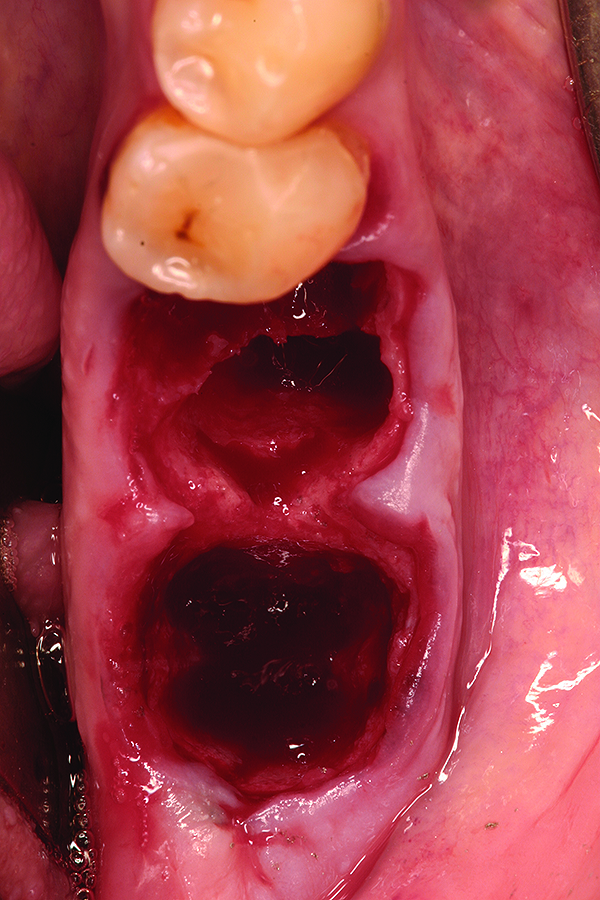

Fig 1. Case 1: Hopeless mandibular first and second molars prior to extraction.

Figure 1

Fig 2. Atraumatic extraction of hopeless mandibular first and second molars.

Figure 2